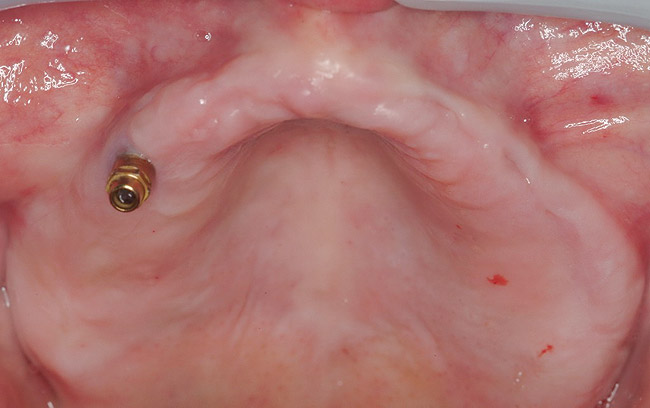

Figure 13  In Case 2, a mini implant in the maxillary right first bicuspid position served as a retentive anchor for a full denture.

Figure 13

Figure 14

A 54-year-old woman who had been edentulous for more than 10 years presented to the author’s practice. She had previously undergone implant therapy in her mandibular left posterior sextant, and recently had a “mini”-implant procedure in the remainder of her mandibular arch, supporting a removable prosthesis. She also had several mini implants placed in her maxilla and an overdenture fabricated. Three of the four implants did not achieve osseointegration and were removed by her dentist. The mini implant in the maxillary right first bicuspid position served as a retentive anchor for a full denture (Figure 13 and Figure 14).